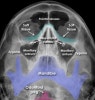

(1) Dolan & Jacoby’s line

| 1 : Orbital line 2 : Zygomatic line 3 : Maxillary line |

(2) McGrigor-Campbell lines

| Red line Passes through the zygomatico-frontal sutures and across the upper edge of the orbits Orange line Follows the zygomatic arch, crosses the zygomatic bone and follows the inferior orbital margins to the opposite side Green line Passes through the condyle (1) and coronoid process (2) of the mandible and through the lateral and medial walls of the maxillary antra on each side Midline Used to assess symmetry |